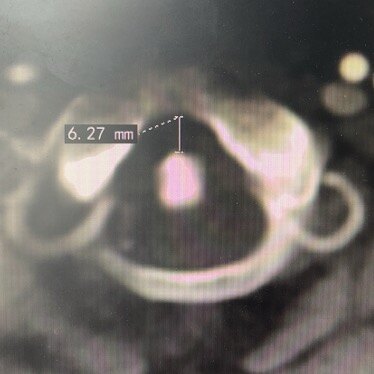

寰樞椎脫位是一種嚴(yán)重疾病,由于寰椎向前或向后脫位,引起上部頸髓受壓,導(dǎo)致患者出現(xiàn)四肢癱瘓,甚至呼吸肌麻痹而死亡,必須及時(shí)進(jìn)行救治。寰樞椎脫位的病因可分為外傷性、先天性和病理性三大類。在我國(guó),以外傷性寰樞椎脫位多見(jiàn),先天畸形性寰樞椎脫位其次,而病理性寰樞椎脫位相對(duì)少見(jiàn)。外傷性寰樞椎脫位占頸部骨折脫位的10%~14%。常見(jiàn)原因有齒突骨折和橫韌帶損傷,橫韌帶損傷可分為韌帶本身的斷裂以及骨附著部撕脫。此外翼狀韌帶損傷可引起寰樞旋轉(zhuǎn)不穩(wěn)。關(guān)節(jié)囊、覆膜、寰樞副韌帶等其他韌帶損傷以及某些寰椎和樞椎體骨折也會(huì)導(dǎo)致寰樞椎不穩(wěn)與脫位。先天性寰樞椎脫位的常見(jiàn)原因?yàn)辇X突發(fā)育異常、先天性寰枕融合、Klippel-Feil綜合征、顱底凹陷等先天畸形。其中齒突畸形最為常見(jiàn),包括齒突缺如、齒突發(fā)育不全和游離齒突等三種類型。齒突生理功能不全或喪失,使齒突在寰椎前弓和橫韌帶之間的穩(wěn)定的扣鎖關(guān)系減弱或消失,使寰椎在樞椎上活動(dòng)范圍異常增大。而在寰枕融合或Klippel-Feil綜合征或顱底凹陷患者,寰樞關(guān)節(jié)負(fù)荷增加,代償性活動(dòng)加大,累積性勞損將使寰樞間韌帶和關(guān)節(jié)囊松弛,逐漸發(fā)生寰樞椎不穩(wěn)和脫位。引起寰樞椎脫位與不穩(wěn)的病理性因素較常見(jiàn)的有感染性炎癥和類風(fēng)濕關(guān)節(jié)炎。蔓延至寰樞椎的感染性炎癥所致脫位與不穩(wěn)絕大多數(shù)發(fā)生于兒童,通常稱為自發(fā)性寰樞椎脫位,其機(jī)制為炎性因素導(dǎo)致關(guān)節(jié)囊和周圍韌帶松弛,并發(fā)的肌肉痙攣及持續(xù)的頸項(xiàng)強(qiáng)直也加劇脫位。類風(fēng)濕關(guān)節(jié)炎引起的寰樞椎脫位與不穩(wěn)多為成人,歐美國(guó)家常見(jiàn)而我國(guó)少見(jiàn)。類風(fēng)濕過(guò)程的破壞性炎癥改變和繼發(fā)于脈管炎的組織變性導(dǎo)致韌帶和關(guān)節(jié)囊松弛,這種慢性炎癥過(guò)程還引起鄰近骨破壞和關(guān)節(jié)滑膜肉芽組織形成;寰椎側(cè)塊骨丟失及隨后的樞椎上移導(dǎo)致顱底下沉,陷人的齒突和(或)肉芽組織可構(gòu)成對(duì)延脊髓腹側(cè)的壓迫。另外,結(jié)核和腫瘤等直接破壞骨性和韌帶結(jié)構(gòu),也可引起寰樞椎脫位與不穩(wěn)。按脫位方向可分為前脫位、后脫位和旋轉(zhuǎn)脫位。按能否復(fù)位可分為易復(fù)性、難復(fù)性和不可復(fù)性。經(jīng)頭頸雙向牽引能復(fù)位的為易復(fù)性,頭頸雙向牽引不能完全復(fù)位但減壓松解術(shù)后牽引能復(fù)位的為難復(fù)性,頭頸雙向牽引及減壓松解術(shù)后再牽引仍不能復(fù)位的為不可復(fù)性。陳舊性損傷或畸形多為難復(fù)性和不可復(fù)性脫位,不能復(fù)位的原因有寰樞外側(cè)關(guān)節(jié)交鎖、肉芽瘢痕增生、齒突骨折畸形愈合、寰樞關(guān)節(jié)破壞強(qiáng)直和韌帶的嵌壓等。外傷性寰樞椎脫位有明確的外傷史,但有些患者外傷并不嚴(yán)重而易引起漏診。傷后即刻部分患者即表現(xiàn)出寰樞椎脫位,另一部分則漸進(jìn)出現(xiàn)脫位。臨床表現(xiàn)有:①局部癥狀與體征:頸項(xiàng)肌痙攣和疼痛,頸項(xiàng)活動(dòng)受限;頸部失落感,常需雙手托住下頜,頭部不敢活動(dòng);頭頸部偏斜。②頸髓受壓表現(xiàn):嚴(yán)重的頸髓損傷多因呼吸肌麻痹而死于現(xiàn)場(chǎng),能運(yùn)送至醫(yī)院者多為頸髓不完全性損傷,根據(jù)脊髓損傷的輕重可出現(xiàn)不同程度的四肢感覺(jué)、運(yùn)動(dòng)和反射障礙。③部分患者在外傷后逐漸出現(xiàn)寰樞椎脫位,由于椎動(dòng)脈穿行于橫突孔并從寰椎上方穿出,過(guò)度活動(dòng)可刺激椎動(dòng)脈導(dǎo)致痙攣或閉塞,出現(xiàn)頭暈、一過(guò)性昏迷等椎-基底動(dòng)脈供血不足癥狀。先天畸形性寰樞椎脫位多為無(wú)明顯誘因緩慢發(fā)病,癥狀呈間歇性,反復(fù)多次發(fā)作并緩慢加重。首發(fā)癥狀多為四肢無(wú)力、步態(tài)不穩(wěn)、四肢麻木,四肢麻木可單肢或雙上肢或雙下肢。其次是頭痛、頭暈,頭痛以枕部為多。少數(shù)患者有飲水嗆咳、吞咽困難、聲音嘶啞等。一般體征:短頸畸形、后發(fā)際低、頭頸部活動(dòng)受限、斜頸及翼狀肩等。神經(jīng)癥狀和體征:由于頸椎畸形,椎管狹窄和小腦扁桃體下降自背側(cè)壓迫上頸髓,多出現(xiàn)肢體感覺(jué)運(yùn)動(dòng)障礙和椎體束征,多見(jiàn)下肢肌張力增高、腱反射亢進(jìn)和病理反射等。自發(fā)性寰樞椎脫位大多發(fā)生于小兒,多繼發(fā)于咽喉或枕頸區(qū)感染,常表現(xiàn)為持續(xù)性頸部疼痛及活動(dòng)受限,并呈逐漸緩慢加重,且常為單側(cè)旋轉(zhuǎn)性脫位,早期易復(fù)位,后期可發(fā)展為固定性旋轉(zhuǎn)畸形。類風(fēng)濕寰樞椎脫位具有類風(fēng)濕關(guān)節(jié)炎的病史和癥狀。X線片包括頸椎正側(cè)位、張口位片,必要時(shí)可行動(dòng)態(tài)側(cè)位照片、顱骨照片和一些特殊位置照片。CT可以更清晰的顯示骨性結(jié)構(gòu)及其關(guān)系。MRI可直接顯示脊髓、腦干及小腦等神經(jīng)結(jié)構(gòu)受壓和變性情況,應(yīng)用動(dòng)態(tài)MRI可觀察局部失穩(wěn)對(duì)神經(jīng)的動(dòng)態(tài)刺激或壓迫;MRI也可直接顯示寰椎橫韌帶受損情況。寰齒前間隙:為寰椎前結(jié)節(jié)后緣與齒突前緣間隙。正常成人<3mm,過(guò)屈過(guò)伸時(shí)無(wú)變化;兒童<4mm,過(guò)屈過(guò)伸時(shí)差值<1mm。寰樞椎前脫位或半脫位時(shí)此間隙可增寬,如超過(guò)5mm以上,則考慮有寰椎橫韌帶松弛或斷裂。寰椎兩側(cè)緣與樞椎體兩側(cè)緣正常情況下應(yīng)是連續(xù)的,若發(fā)生同向不連續(xù)則表示寰椎側(cè)方移位;若兩側(cè)離心分離之和>6.9mm,則可能有寰椎橫韌帶斷裂。寰樞椎脫位的診斷通過(guò)影像學(xué)檢查并不困難,關(guān)鍵是骨科醫(yī)師要考慮到此病。外傷性寰樞椎脫位雖然多有明確的外傷史,但在臨床上造成漏診和誤診者并不少見(jiàn),原因?yàn)椋孩俸喜⒌娘B腦外傷干擾了對(duì)頸椎損傷的診斷;②外傷后逐漸出現(xiàn)的寰樞椎脫位,逐漸發(fā)生的脊髓壓迫癥狀;③陳舊性脫位,癥狀體征不典型,外傷史不明確。由于枕頸部先天性畸形臨床表現(xiàn)的多變性,而且癥狀通常隱匿、體征定位困難,故臨床有如下表現(xiàn)應(yīng)懷疑有顱頸交界區(qū)先天性畸形的存在:①青壯年發(fā)病,癥狀間歇呈漸進(jìn)性加重,無(wú)明顯誘因或輕微創(chuàng)傷誘發(fā)發(fā)病。②頭頸部畸形,發(fā)際低平、短頸、頭頸活動(dòng)受限。③枕項(xiàng)疼痛、疲勞感或麻木無(wú)力。④復(fù)雜的難以解釋的神經(jīng)學(xué)癥狀。寰樞椎脫位外科治療的目的為:解除脊髓壓迫,穩(wěn)定脊柱節(jié)段,防止繼發(fā)損傷。非手術(shù)治療的方法有牽引、外固定和功能鍛煉,手術(shù)治療方法通常有減壓復(fù)位術(shù)和內(nèi)固定融合術(shù)。治療方法的選擇取決于寰樞椎脫位的類型、病因以及并發(fā)神經(jīng)損傷的情況。治療程序一般先行牽引,判斷脫位是可復(fù)性還是不可復(fù)性,對(duì)不可復(fù)性脫位需行手術(shù)治療,可復(fù)性脫位根據(jù)病因不同可行手術(shù)治療或非手術(shù)治療;如果非手術(shù)治療效果欠佳,則應(yīng)二期手術(shù)治療。如果存在不可復(fù)位的延脊髓壓迫或伴有腦脊液循環(huán)障礙,應(yīng)盡快行減壓術(shù)。原則上腹側(cè)壓迫經(jīng)口前路減壓,背側(cè)壓迫行后路減壓,減壓的范圍視具體情況可擴(kuò)大到枕骨大孔區(qū)甚至顱后窩。對(duì)于橫韌帶斷裂,如果能確診,應(yīng)一期行寰樞融合術(shù)??梢蓹M韌帶斷裂時(shí),可先行外固定治療。而對(duì)于橫韌帶附著點(diǎn)的撕脫性損傷,因預(yù)后較好,應(yīng)先行外固定。外固定治療3~4月后如存在持續(xù)性不穩(wěn),應(yīng)行寰樞融合術(shù)。先天性寰樞椎脫位,因畸形持續(xù)存在,脫位多為難復(fù)性或不可復(fù)性且呈漸進(jìn)性加重,非手術(shù)治療效果差。因?yàn)轱B頸交界區(qū)畸形多為多種畸形合并存在,先天性寰樞椎脫位與不穩(wěn)常需行枕頸融合術(shù)。自發(fā)性寰樞椎脫位牽引效果好,復(fù)位后予以適當(dāng)外固定并加強(qiáng)功能鍛煉,常能獲得較滿意的療效。類風(fēng)濕關(guān)節(jié)炎引起的寰樞椎脫位,病程為慢性進(jìn)行性,病變累及范圍較廣,可先行非手術(shù)治療,如效果欠佳(存在神經(jīng)壓迫時(shí)),則應(yīng)行減壓融合術(shù)。對(duì)于結(jié)核或腫瘤引起的寰樞椎脫位與不穩(wěn),除治療脫位與不穩(wěn)外,還應(yīng)處理原發(fā)病灶。